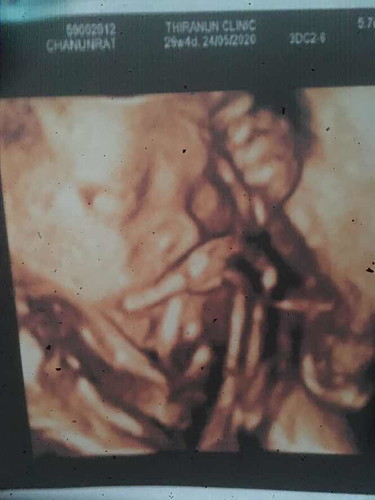

หนูชอบนอนท่านี้คับ มือปิดหน้าปิดตาไปหมด ลูกชาย 29+4สัปดาห์ ??

น้องคลอดมาก็จะชอบท่านี้เหมือนบ้านนี้เลยค่ะแม่ ตอนซาวน์เอามือปิดหน้าตลอดเลย

ซาวกี่รอบก็เจอแต่ท่านี้ค่ะแม่